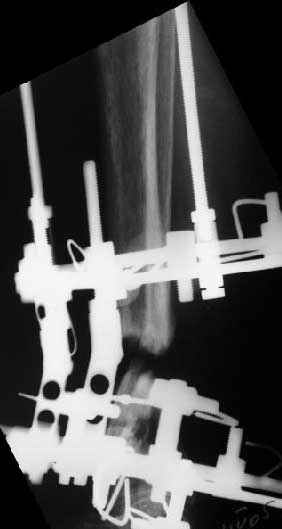

> In attachment - x-rays at the end of alignment, the surgery, and

> result. The nail was cut to 23 cm. Four 45 degree holes were

> pre-drilled at the distal nail tip. The nail was locked statically

> after some impaction.

Amazing! How can you find the pathway of the nail through all those wires and the distal screws through so much hardware?

NL> Amazing! How can you find the pathway of the nail through all those wires

NL> and the distal screws through so much hardware?

Some wires were intentionally inserted to leave needed space for the nail, some were removed at the moment of nail insertion. I inserted one distal screw and then removed the frame, then inserted rest ones.